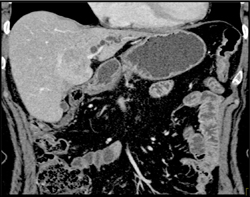

Diagnosis

Hepatoma